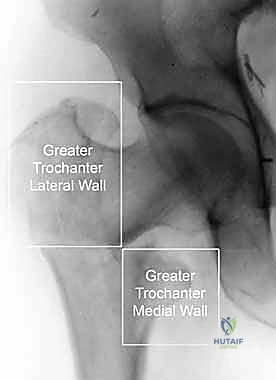

لفهم طبيعة الكسر وكيفية عمل التسمير النخاعي، يجب أن نتعرف على تشريح عظمة الفخذ، وهي أطول وأقوى عظمة في جسم الإنسان. ينقسم الجزء القريب من عظمة الفخذ (Proximal Femur) إلى عدة مناطق رئيسية:

1. رأس الفخذ (Femoral Head): الجزء الكروي الذي يستقر في تجويف الحوض ليُشكل مفصل الورك.

2. عنق الفخذ (Femoral Neck): المنطقة الضيقة التي تربط الرأس ببقية العظمة، وهي عرضة للكسور خاصة عند كبار السن.

3. المدور الكبير والمدور الصغير (Greater and Lesser Trochanters): نتوءات عظمية بارزة تعمل كنقاط ارتكاز واتصال للعضلات القوية المحركة للورك والفخذ.

4. منطقة ما تحت المدورين (Subtrochanteric Region): الجزء من العظمة الذي يقع أسفل المدور الصغير مباشرة، وهو يتحمل ضغوطاً ميكانيكية هائلة أثناء المشي.

كسور هذه المنطقة تُعرف طبياً بكسور ما بين المدورين (Intertrochanteric Fractures) أو كسور ما تحت المدورين (Subtrochanteric Fractures). ونظراً للضغوط الهائلة التي تتعرض لها هذه المنطقة، فإن تثبيتها يتطلب غرسة قوية قادرة على تحمل الوزن، وهو ما يوفره المسمار النخاعي الرأسي الفخذي بكفاءة عالية.